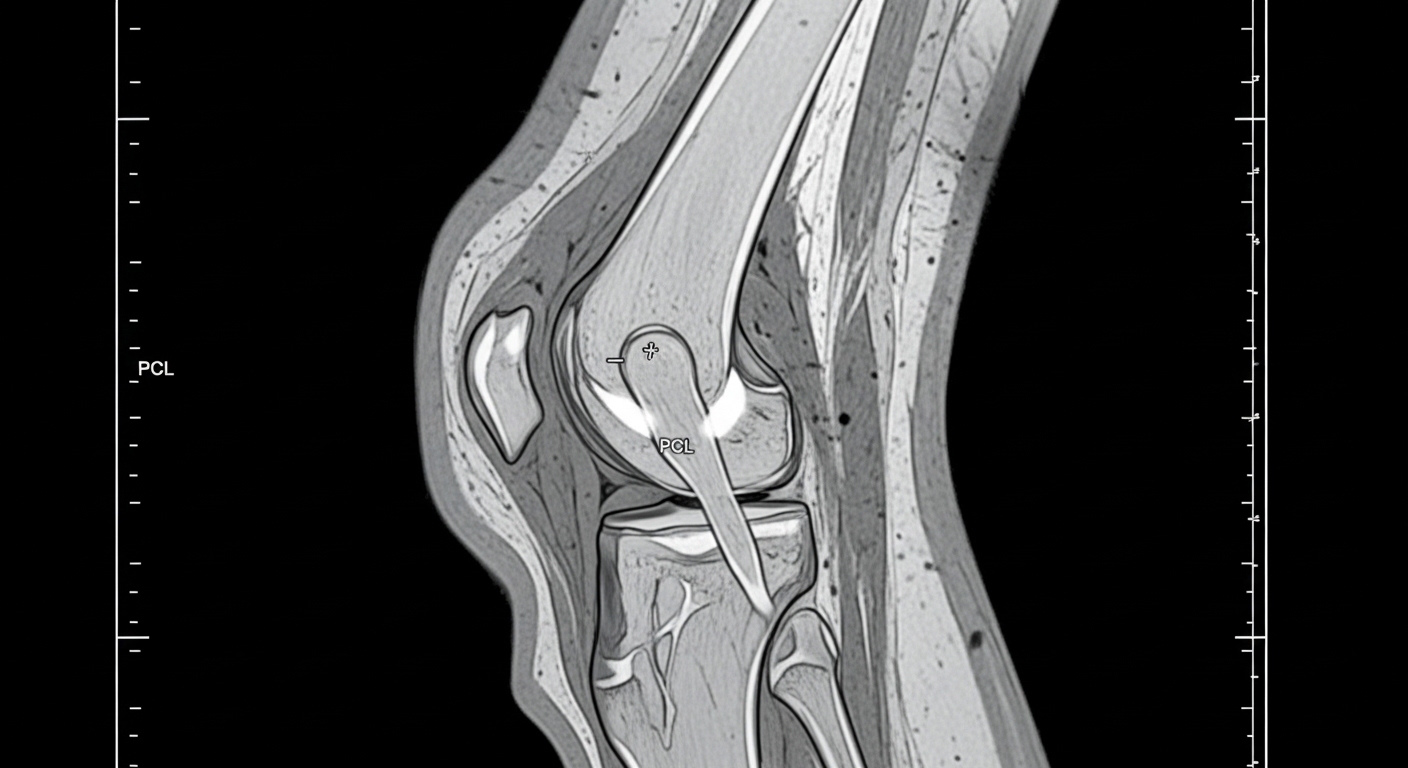

무릎 인공관절 수술은 연골이 심하게 닳아 일상생활이 어려울 때, 손상된 무릎 관절을 금속과 플라스틱 재질의 인공관절로 교체하는 수술이에요. 주로 퇴행성 관절염이 상당히 진행된 분들에게 권고된답니다.

수술 방식은 크게 두 가지로 나뉘어요. 전치환술(TKA)은 무릎 관절 전체를 인공관절로 바꾸는 방식이고, 부분치환술(PKA)은 손상된 한쪽 구획만 교체해요. 최근에는 로봇 보조 수술 방식도 많이 도입되어, 정밀도와 수명 면에서 기존 수술보다 개선된 결과를 보여주고 있어요.